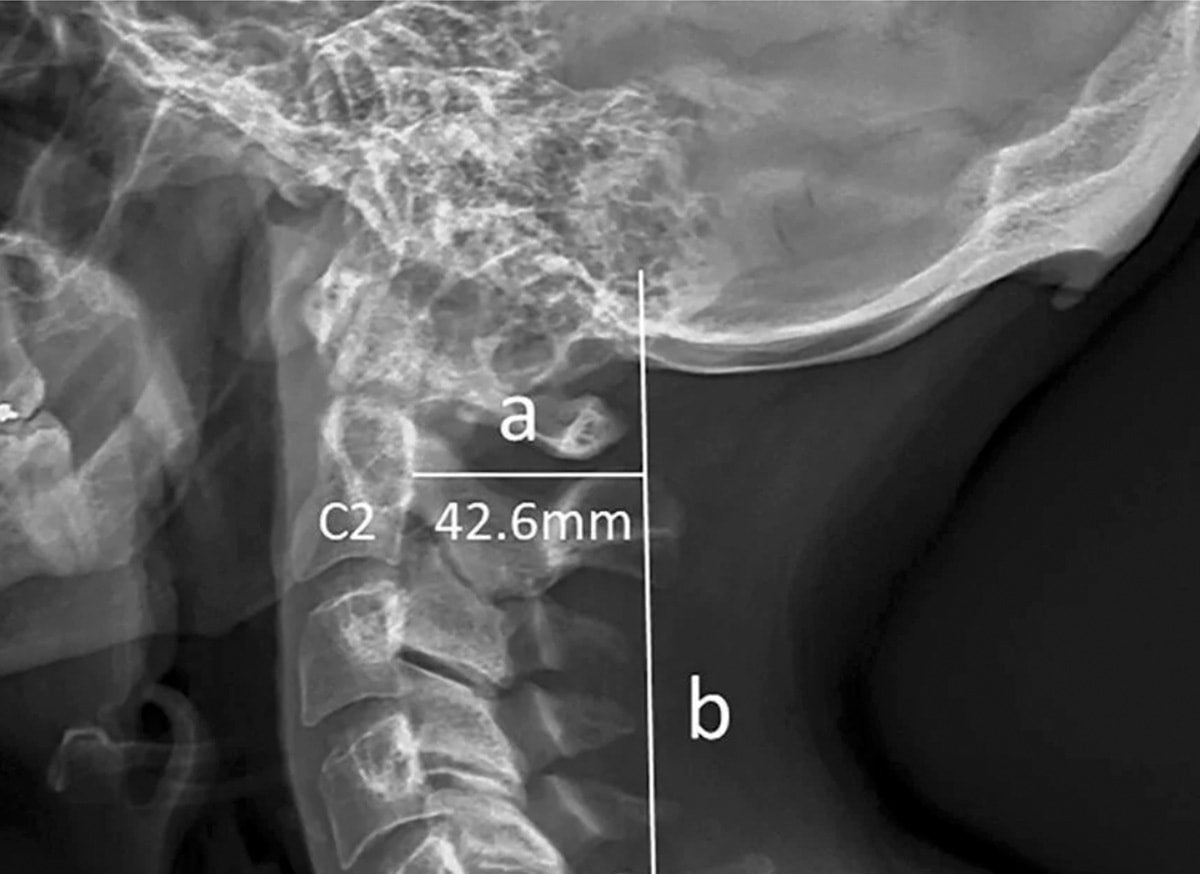

Recently, news emerged about a troubling finding: young people growing a “head horn.” Was this the physical manifestation of too much hand-held screen time? Are our bodies changing, evolving, based on our daily activities? Well, maybe the “head-horn” was bunk, but our bodies being shaped by our environments and evolving based on our activities… that is not. In this two-part post, Dr. Osler looks at how the environment and our changing activities impacts our bodies, and our health.